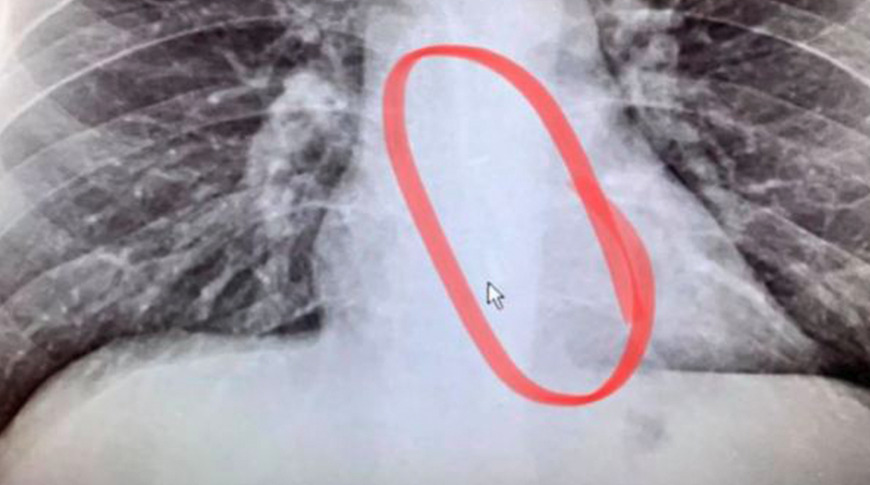

Arrivato in ospedale, i medici hanno eseguito una radiografia al torace dell’uomo e hanno confermato che l’AirPod si trovava nel suo esofago e hanno tempestivamente effettuato un’endoscopia di emergenza per rimuovere l’oggetto.